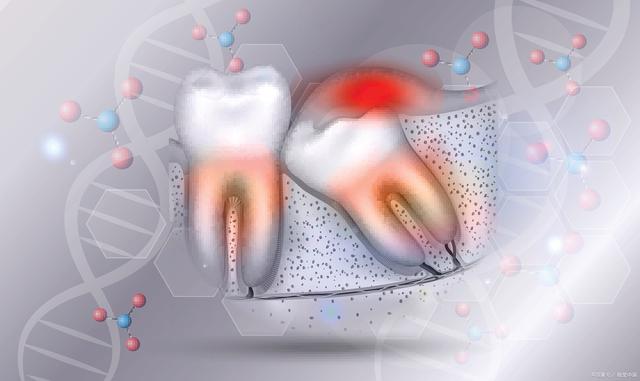

牙齿龋齿的预防和治疗

牙齿龋齿是口腔中最常见的疾病之一,主要由于口腔内的细菌分解糖分而产生的酸腐蚀牙齿。预防牙齿龋齿的方法包括:

牙周病的预防和治疗

牙周病是由于牙周组织受到细菌感染而引起的一系列疾病,包括牙龈炎、牙周炎和牙周组织萎缩等。预防牙周病的方法包括:

牙齿敏感的预防和治疗

牙齿敏感是指牙齿在刺激下出现疼痛或不适的症状,主要由于牙齿表面的牙釉质磨损或龋齿等问题所导致。预防牙齿敏感的方法包括: